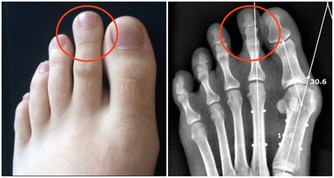

八、骨質疏鬆檢查

測中指間距,兩手向兩側水平伸直,測量兩手中指指尖之間的直線距離,然後再測量身高。如果身高比兩指間的距離少,說明骨質疏鬆和骨密度減少。身高比指尖距離少2-3公分者,照X線相片可顯示為明顯的骨質疏鬆。